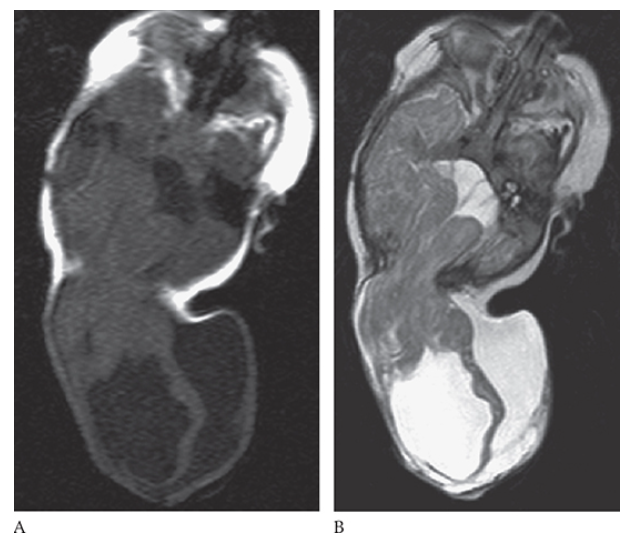

What is A

Encephalocele. Axial T1W and T2W

What is B

Encephalocele. Axial T1W images showing herniation of the brain through a defect in the posterior skull.